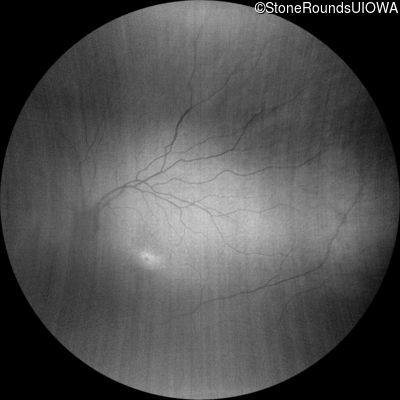

Infrared Fundus Photograph - Right - 10/200

Exemplar

Infrared Fundus Photograph - Left - 10/100